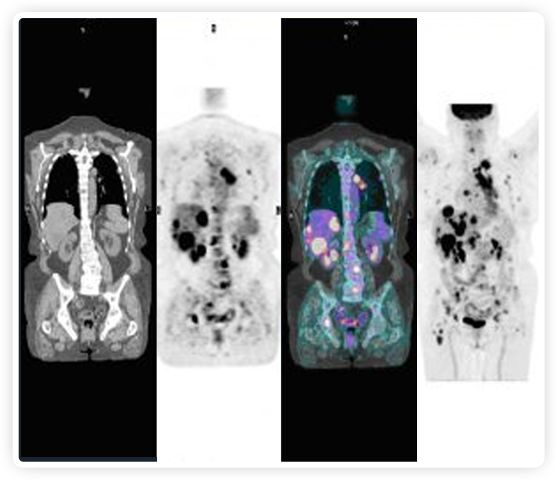

PET+放療共同治療

RefleXion將PET成像與立體定向放射治療相結(jié)合。在注射示蹤劑后,RefleXion的技術基于示蹤劑信號實時地在一個或多個目標上引導治療性X射線。使用這種專有方法,RefleXion的平臺有可能比現(xiàn)有系統(tǒng)向癌癥病變提供更高劑量的輻射,并改善周圍健康組織的保護。

有這么大的潛力,為什么以前沒有做過?一個原因是使用傳統(tǒng)PET技術生成高質(zhì)量圖像需要的時間較長,這使得它不適合實現(xiàn)實時器官運動追蹤。

為了避免PET長圖像采集時間,RefleXion開發(fā)了一項專利技術使用重合的PET光子對來指導放射治療束,因為實時檢測發(fā)射的光子,為生物指導提供了一種時間有效的方法。

“RefleXion系統(tǒng)是第一個也是唯一一個讓患者的腫瘤引導自己治療和破壞的系統(tǒng),”RefleXion的創(chuàng)始人兼首席技術官Samuel Mazin博士說?!拔覀兊哪繕耸峭ㄟ^單獨治療或與免疫療法和其他晚期抗癌藥物一起消除全身疾病。我們相信這可能有助于減少世界衛(wèi)生組織預計在2030年發(fā)生的超過1300萬的全球癌癥死亡事件?!贝送?,RefleXion的技術已經(jīng)被證明可以簡化和自動化放射治療過程的許多要素。